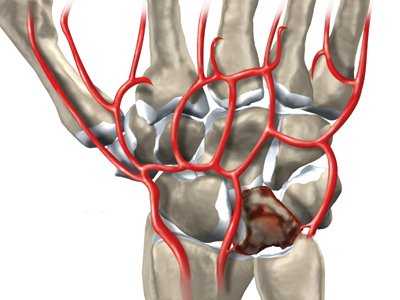

Некроз полулунной кости при болезни Кинбека

Считается, что причиной развития заболевания может служить однократная травма (падение на ладонь или кисть), а также постоянная травматизация (микротравматизация), что может привести к нарушению кровоснабжения костей запястья.

Поэтому болезнь Кинбека чаще встречается у людей, чья физическая активность связана с высокой нагрузкой на область лучезапястного сустава. Полулунная кость занимает центральное место в запястье, располагаясь между головчатой костью запястья и лучевой костью, и поэтому больше других костей травмируется при физической нагрузке. Заболевание развивается постепенно, и встречается чаще всего у мужчин рабочих профессий: рубщиков, столяров, слесарей, крановщиков, лиц, работающих с вибрирующими устройствами (отбойные молотки, перфораторы, и т.п.). НО, может возникать и у женщин других специальностей: парикмахер, повар, пекарь, кондитер, косметолог, визажист, массажист и т.п. Чаще всего поражается ведущая рука (у правшей - правая, у левшей - левая) при болезни Кинбека. Еще одна из причин развития болезни Кинбека - врожденная короткая локтевая кость. При таком случае давление на полулунную кость возрастает и может развиться остеонекроз полулунной кости (болезнь Кинбека).

Сущность болезни состоит в постепенно нарастающем асептическом некрозе (или, точнее остеонекрозе) полулунной кости, который со временем приводит к ее фрагментации и полному разрушению. Все это сопровождается болью в запястье, в области лучезапястного сустава. Боль усиливается при движениях и возрастает по мере прогрессирования заболевания.

Дегенеративные изменения кости провоцируются ухудшением локального кровоснабжения вследствие перегрузки и травматических повреждений. Вокруг очага дегенерации образуется зона отека, что также негативно влияет на местное кровообращение. Процессы разрушения превалируют над процессами восстановления. Из-за поражения значительной части кости даже при небольших травматических воздействиях возникают патологические переломы.

На фоне импрессионных переломов продолжает снижаться прочность костной ткани. На суставной поверхности образуются участки некроза и фиброзного перерождения, деформации усугубляются. Кость фрагментируется. Суставные поверхности утрачивают конгруэнтность, прогрессируют артрозные изменения. Степень окончательной деформации варьируется от незначительной до грубой.